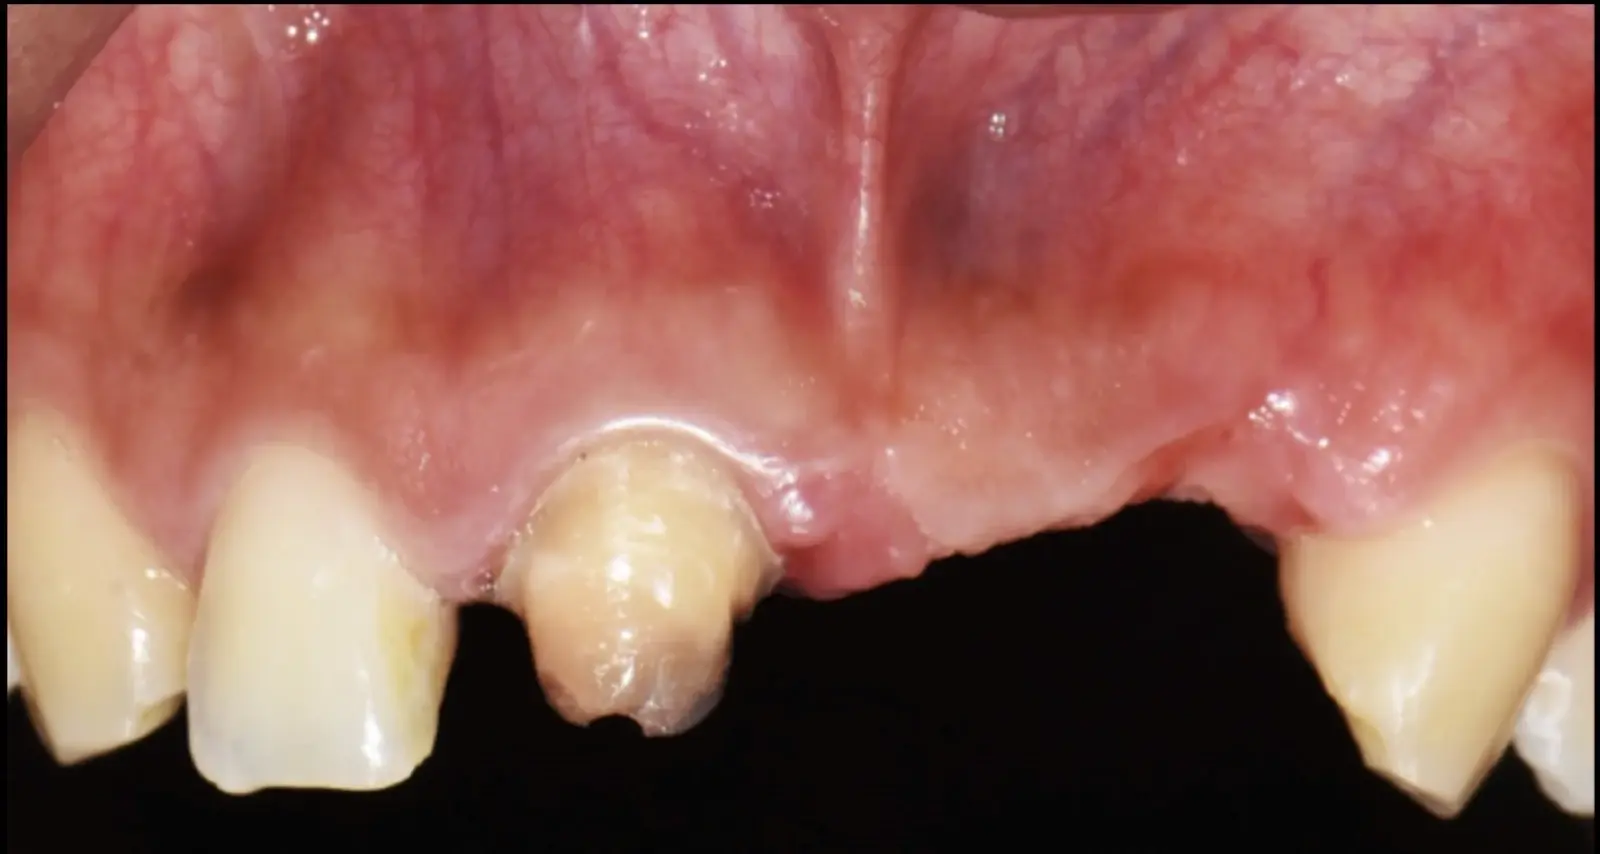

Paciente de sexo femenino de 36 años de edad, llega a la consulta por presentar una restauración protésica inadecuada. En el examen clínico se observa una restauración protésica provisional acrílica sobre las piezas 1.1 y 2.2. Adicionalmente, se aprecia recesión gingival a nivel de la pieza 2.2 y deficiencia horizontal severa de reborde a nivel de la zona edéntula correspondiente a la pieza 2.1. En la evaluación tomográfica se observa ausencia total de tabla ósea vestibular en la pieza 2.2, y se corrobora el déficit en la zona edéntula de la pieza 2.1, para lo cual se indica una reconstrucción de estructuras óseas con hueso en bloque de origen bovino y posteriormente la colocación de implantes dentales.

Figura 34. Vista frontal donde se observa deficiencia vertical del reborde óseo a nivel de las piezas 2.1, 2.2.

Figura 46. Control a los 10 días post cirugía.